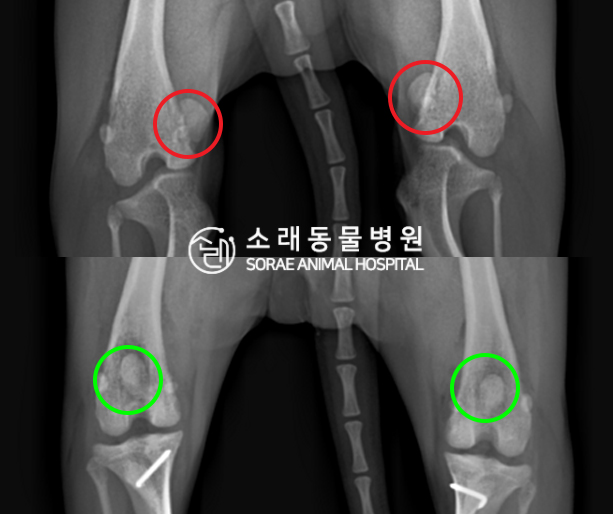

수술전과 수술후에 촬영한 봄이의 슬개골

방사선 사진입니다. 나란히 놓고 비교해보니

슬개골의 위치에 확연한 차이가 있는 것을

확인해 볼 수 있는데요. 내측으로 탈구되어 있던

슬개골이 원래 제자리인 활차구에 예쁘게

자리 잡고 있는 모습을 확인할 수 있었습니다.